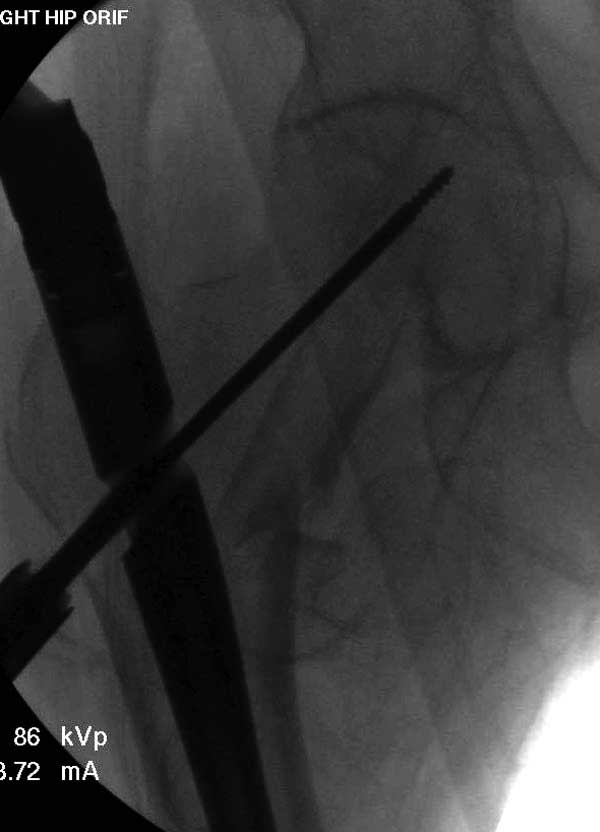

Первые снимки показывают технические погрешности установки DHS. Не была достигнута репозиция, конечность в флексии и шейка в ротации. Сегодня все меньше обращают внимание на параметры для оценки репозиции (S контуры Lowell в обеих проекциях и Garden Alignment Index, в норме 155 и 180 градусов), хотя такие простые тесты помогли бы дорепонировать смещение. Винт находится сзади в головке, что при нагрузке поменяет вектор и вместо компрессии в линии перелома срежет головку-Cut Out!

Имя     : 31 IT fx LT injury CRM reduction.jpg

Тип     : image/jpg

Размер  : 27261 байтов

Описание: отсутствует

Url     : http://weborto.net:8080/pipermail/ortho/attachments/20120509/52aada75/attachment-0051.jpg